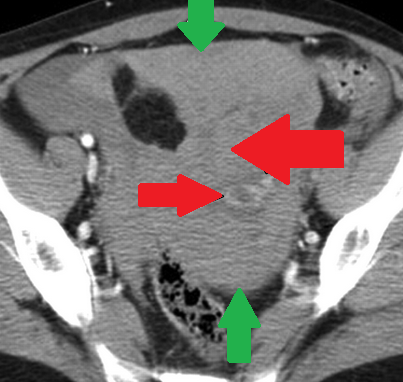

Αριστερό περινεφρικό αιμάτωμα και δεξιό αιμάτωμα λαγονοψοΐτη — αντιπηκτική αγωγή (Ευγενική παραχώρηση Dr. V. Penopoulos)